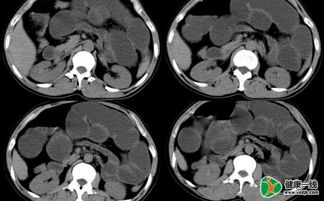

(2) X線檢查:一般梗阻發(fā)生4?6小時后,立位或側(cè)臥位腹部透視或攝片檢查可見脹 氣腸袢及多個液平面。空腸脹氣可呈“魚骨刺”狀;回腸脹氣可見階梯狀液平面;結(jié)腸脹氣 腹部周邊顯示結(jié)腸袋形。

鋇劑灌腸可用于疑有結(jié)腸梗阻的患者,可顯示梗阻的部位和性 質(zhì)。小腸梗阻時忌用胃腸造影檢查。